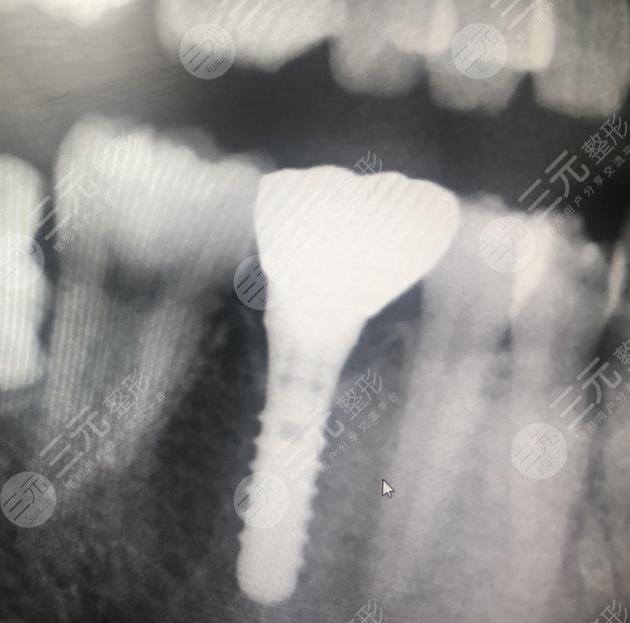

在聽了醫(yī)生的介紹之后,我決定選擇使用這種方法,沒想到這種方法確實(shí)GET了不錯的目的,現(xiàn)在我種植牙齒之后已經(jīng)有快兩年的時間了,沒有出現(xiàn)任何的副作用,平時也沒有出現(xiàn)牙齒疼痛的現(xiàn)象。